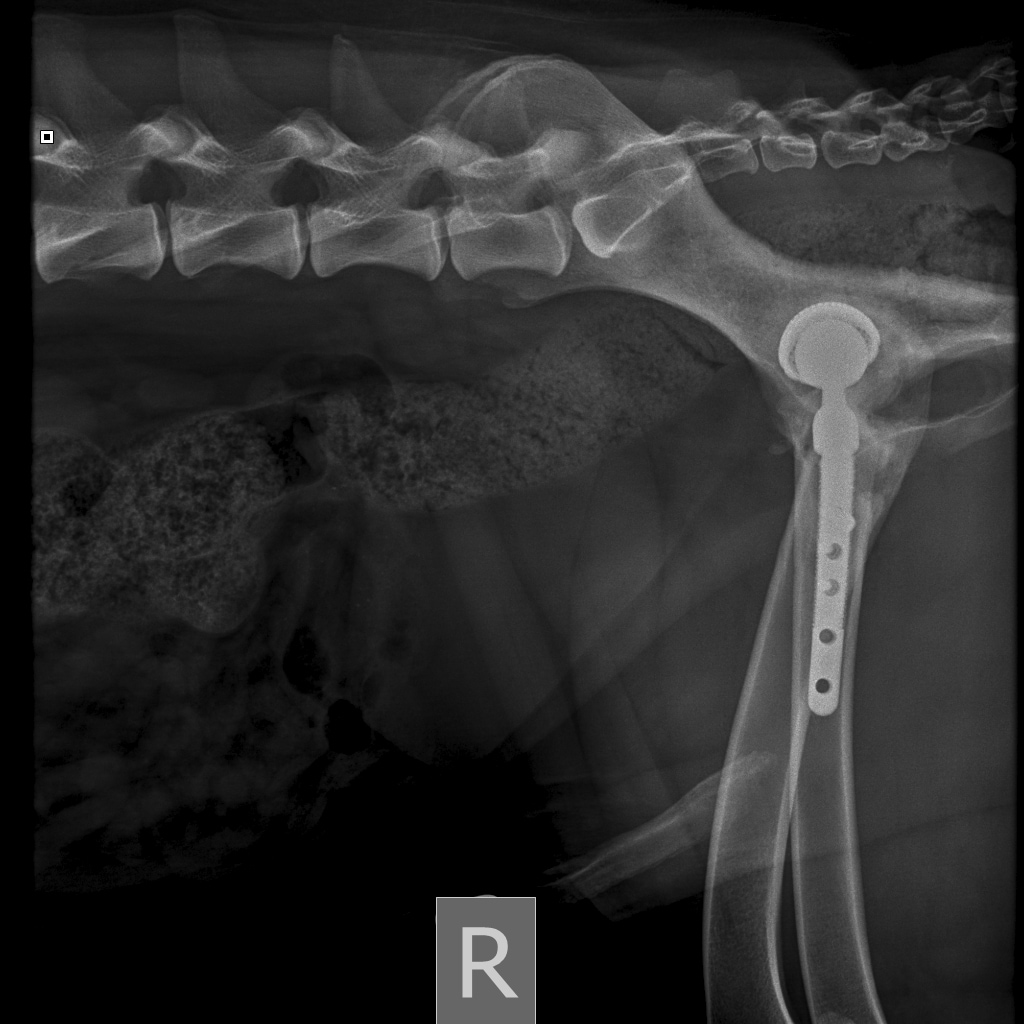

26 августа к 10 утра голодными, нас ждут на контрольный рентген в клинике на Вернадского.

Рентген будет под седацией

За время противовоспалительной терапии снизилось воспаление и в левом тазобедренном суставе, но увы, форма головки бедренной кости и состояние шейки бедра , лучше не стали:(((

Операция однозначно нужна.

Снимки столь качественные, что их можно в учебник

Перевели все собранные на Бруно деньги на счет клиники.

Готовимся ко второй операции 3 октября

Съездили мы с Бруно к врачу. Скажу честно, и врач очень расстроился, увидев состояние шва, и мы с Ирой вслед за врачом. Илья Федорович очень опасался, что свищ дошел до сустава, а это самое плохое осложнение, которое можно себе представить. Забрали Бруняшу, сделали наркоз, рентген под наркозом, всё вычистили, наложили швы. По словам хирурга, внешне пока до сустава не дошло, воспалительный процесс, вызванный разлизанным швом и попаданием туда инфекции, затронул только мягкие ткани. Но бакпосев взяли. Будет готов через 5-10 дней. Ждем и надеемся. А пока продолжаем пить антибиотики, обрабатывать дренаж, который вставили в шов во время операции сегодня, беречь шов как зеницу ока.